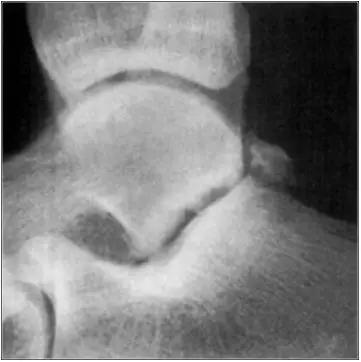

- 放射学表现主要为胫骨前下缘与距骨颈部前上缘鸟嘴样骨刺形成。

放射学表现主要为胫骨前下缘与距骨颈部前上缘鸟嘴样骨刺形成

- Ⅰ度:滑膜撞击,X线片显示有炎性反应,骨刺大小为3mm;

- Ⅱ度:骨软骨反应性骨赘>3mm;

- Ⅲ度:严重的外生骨赘,可伴有或不伴有碎裂, 在距骨背侧可见继发性骨赘,常伴有骨赘的碎裂;

- Ⅳ度:距骨和胫骨关节骨性关节炎改变。